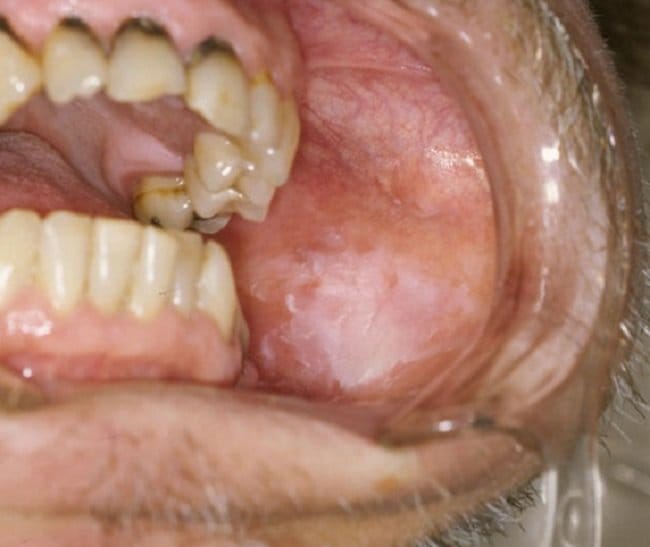

Leukoplakia ditandai dengan timbulnya bercak di dalam mulut. Bercak ini dapat berkembang perlahan dalam beberapa minggu atau bulan.

Bercak pada leukoplakia biasa umumnya timbul pada lidah, sebelah dalam pipi, langit-langit mulut, serta di bawah lidah (dasar mulut). Sementara pada leukoplakia berambut, bercak umumnya muncul di bagian samping lidah.

Adapun ciri bercak pada leukoplakia antara lain:

- Berwarna putih atau putih keabuan, yang tidak bisa hilang dengan sikat gigi atau kumur

- Bisa bertekstur tidak rata atau halus

- Tebal dan keras bila diraba

- Timbul bersama dengan bercak merah yang menonjol, yang bisa menjadi pertanda awal kanker

Meski tidak menimbulkan nyeri, bercak ini bisa sensitif terhadap panas, makanan pedas, atau sentuhan.